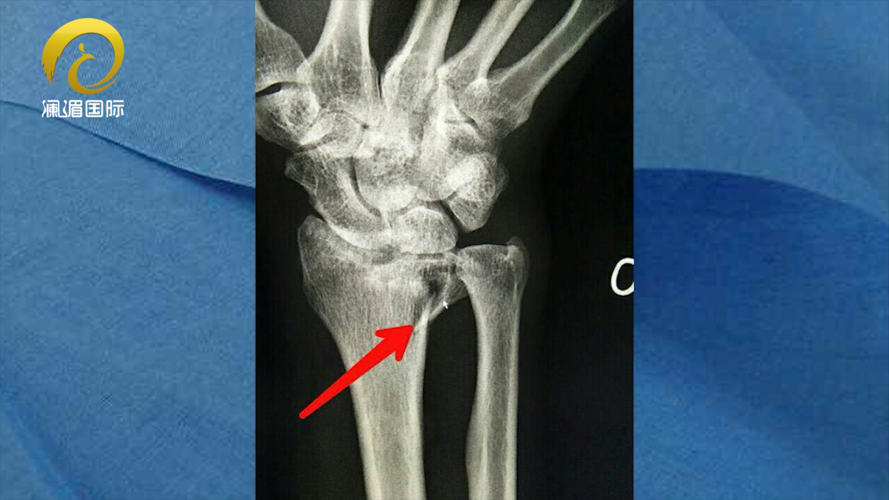

桡骨远端骨折

左桡骨远端骨折

左桡骨远端粉碎性骨折

左桡骨粉碎性骨折图片

左尺桡骨远端骨折图片